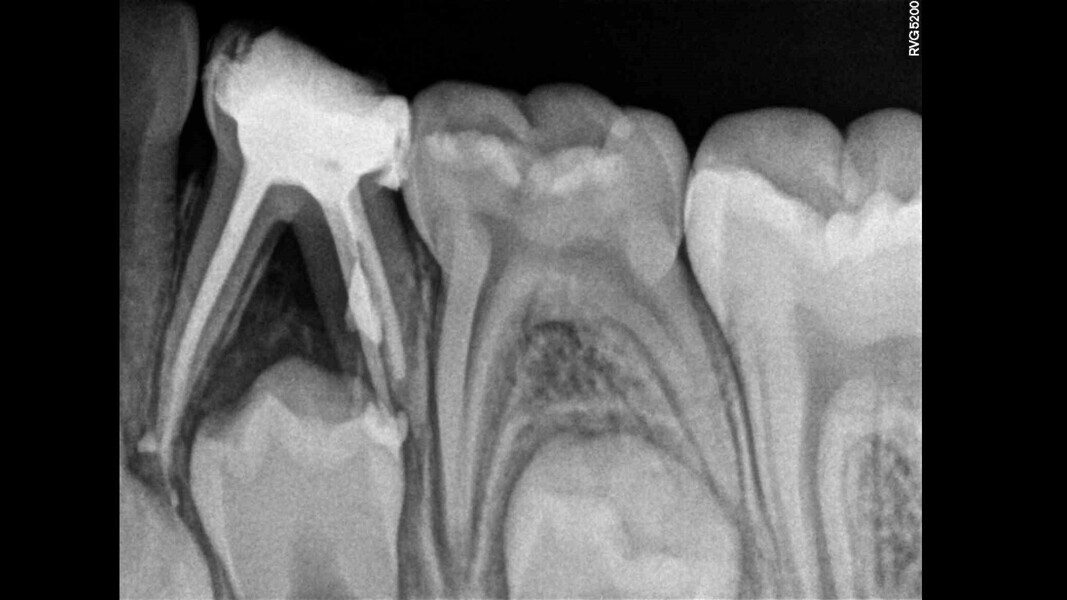

Case 1 (Figs. 1–4)

This female patient was 4 years and 7 months old and presented with pain that had lasted for several days affecting the mandibular right second primary molar. On clinical examination, a buccal gingival swelling and facial initial oedema were noted, and the tooth was found to have deep occlusal decay. Pulp necrosis and a symptomatic apical abscess were diagnosed. The patient was prescribed medication to control acute infection and rescheduled after the antibiotic treatment. At the second appointment, no pain was reported and the buccal abscess had partially receded. A decision was made to perform pulpectomy and restoration. Over-extrusion of the obturation material was observed. The 15-month re-evaluation confirmed no clinical or radiological signs of disease, and bone deposition was evident in the furcal area.